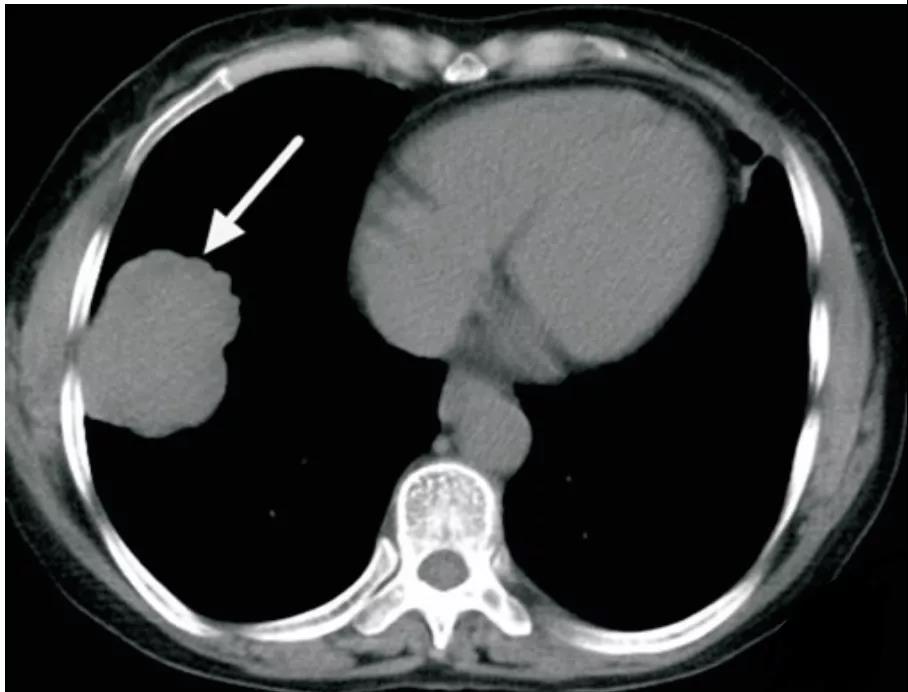

硬化性肺细胞瘤

多为单发孤立病灶,偶有多发,病灶呈圆形或类圆形,边缘清楚,密度均匀,多无毛刺,可见浅分叶,部分可见钙化、囊性变。

增强扫描病灶强化方式及程度与肿瘤成分及微血管数量相关,可表现为均匀显著强化,或不均匀轻度强化

可见特征性血管贴边征(图 2)和周围血管包绕征,即增强动脉期见病灶边缘明显强化的点状血管断面

可伴特征性尾征(图 3),即占位边缘的尾状突起,多位于近端靠近肺门一侧

另可见特征性空气新月征,上述可帮助与其他良性肿瘤及肺癌鉴别